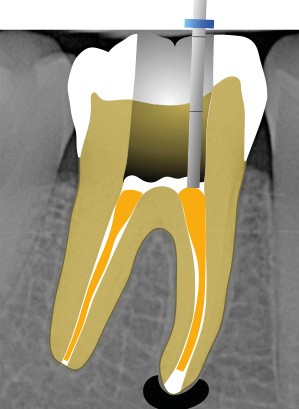

Ce type de perforation est également la plupart du temps iatrogénique et survient lors de la recherche ou de la mise en forme canalaire, lors de la préparation pour un logement de tenon radiculaire. Situées au niveau du plancher pulpaire des dents pluriradiculées, ou au niveau des entrées canalaires des dents monoradiculées ou pluriradiculées, il s’agit le plus souvent de perforations à quatre parois. Si la perforation survient en cours de traitement, elle doit être gérée immédiatement pour un meilleur pronostic (fig. 4). Néanmoins, il est important de prendre en compte l’épaisseur résiduelle du plancher. Si le plancher est trop fin, il ne sera pas possible d’envisager de traiter la perforation.

17. reconstitution coronaire étanche à l’aide d’un CVIMAR ou d’un composite (fig. 5).